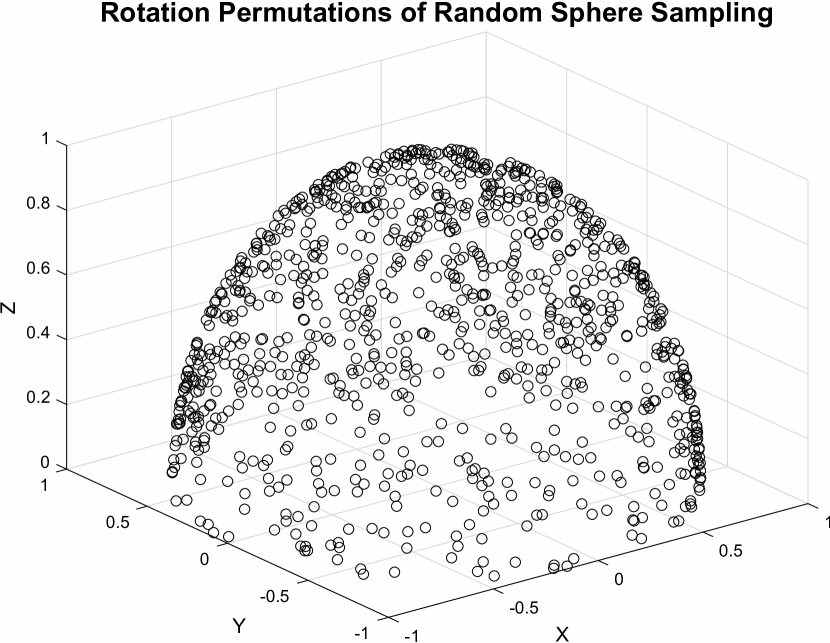

To capture a dense permutation of , we rotate the sampling planes about the origin whilst keeping the volume static. Ideally, all rotational permutations should be random and evenly spaced on the surface of a unit sphere. Uniform sampling of polar co-ordinates, , causes denser sampling near the poles. This can lead to an imbalance of training samples. Thus we use Fibonacci sphere sampling [5], which allows each point to represent approximately the same area. Thus sampling normals can be calculated by , where and , . is the golden ratio, as , and is defined as .

For both, training and validation, only one hemisphere needs to be sampled due to symmetry constraints. Sampling planes with normals in the one hemisphere result in the same image as sampling planes with normals in the other hemisphere albeit mirrored.

0..1 Data generation illustration

Figures 7 to 7 illustrate our data generation sampling strategies and shows the new Z-axis, i.e. normals, of the sampling planes with respect to the origin.